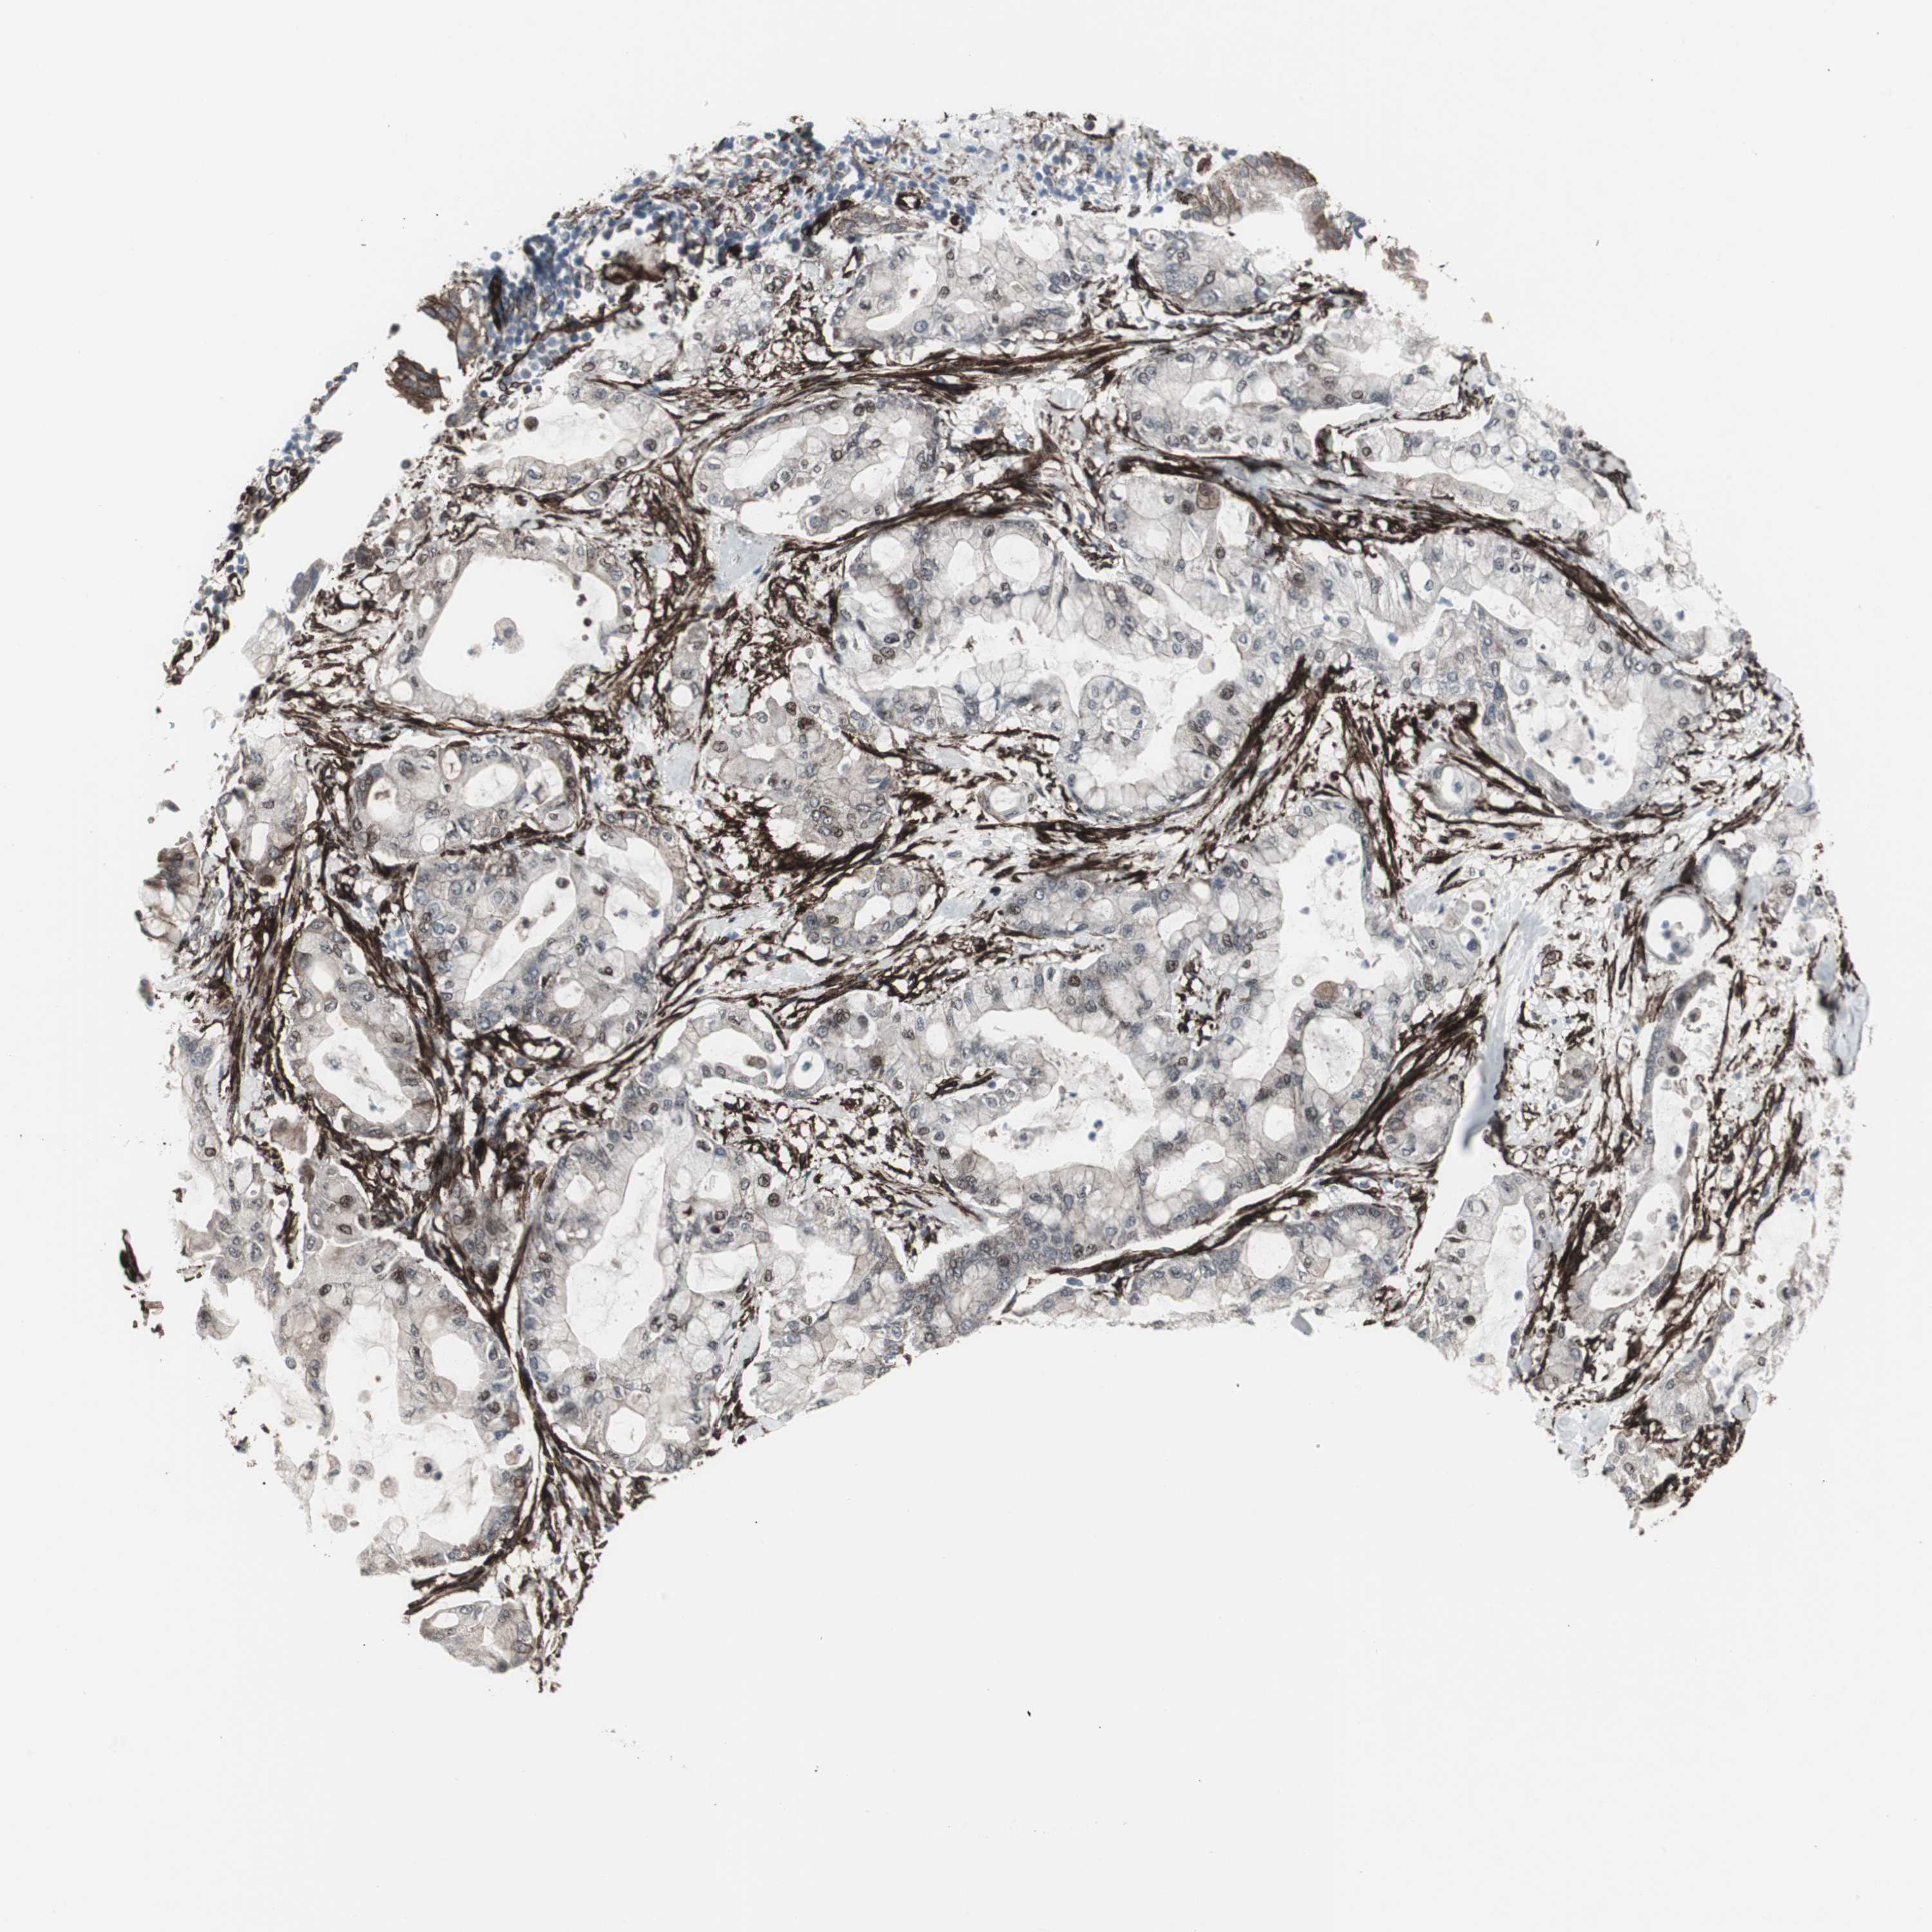

PANCREATIC CANCER - Protein expressioni

A mouse-over function shows sample information and annotation data. Click on an image to view it in a full screen mode. Samples can be filtered based on level of antibody staining by selecting one or several of the following categories: high, medium, low and not detected. The assay and annotation is described here.

Note that samples used for immunohistochemistry by the Human Protein Atlas do not correspond to samples in the TCGA dataset.

Antibody stainingi

Antibody staining in the annotated cell types in the current human tissue is reported as not detected, low, medium, or high, based on conventional immunohistochemistry profiling in selected tissues. This score is based on the combination of the staining intensity and fraction of stained cells.

Each image is clickable and will lead to virtual microscopy that enables deeper exploration of all samples and also displays staining intensity scores, fraction scores and subcellular localization as well as patient and tissue information for each sample.

Antibody CAB005579

Staining

High

Medium

Low

Not detected

Intensity

Strong

Moderate

Weak

Negative

Quantity

>75%

75%-25%

<25%

None

Location

Nuclear

Cytoplasmic/membranous

Cytoplasmic/membranous,nuclear

Adenocarcinoma, NOS

Adenocarcinoma, metastatic, NOS